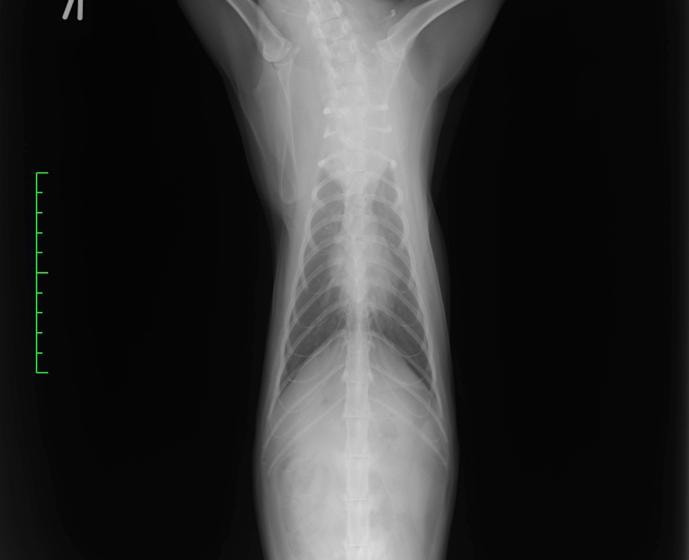

前縦隔型リンパ腫(低分化型) 雑種猫 3歳 ♀猫白血病ウイルス陽性

主訴:食欲低下、えずき、喉元の喘鳴音

身体検査所見:軽度脱水、可視粘膜色正常、心肺音異常なし、腹腔内触知物なし、体表リンパ節腫脹なし

診断:胸部レントゲン検査にて、前縦隔領域に不透過性亢進領域を確認しエコー検査にてFNAを実施。細胞診の結果「低〜中分化型リンパ腫」と診断

治療および経過 :多剤併用療法(UW25プロトコール)を開始。一般状態の改善が認められており、現在も治療中です。

前胸部にみられた不透過性領域の退縮が認められます

猫の前縦隔型リンパ腫は発症に猫白血病ウイルスとの関連があるとされているリンパ腫です。以前は猫のリンパ腫の大部分を占めていましたが、近年は猫白血病ウイルスに罹患している猫が減少している影響により、前縦隔型リンパ腫も減少傾向にあると言われています。前述の通り治療に関する予後や報告は少ないものの、他のリンパ腫と同様に抗がん剤治療への反応がみられるとされています。